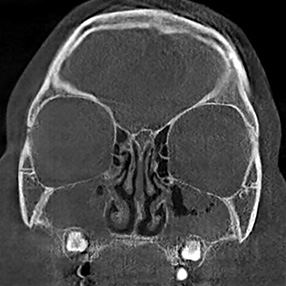

※ 축농증 수술 후 생길 수 있는 부작용으로는 출혈, 감염, 염증이 있을 수 있습니다.

본 사진은 의료기관에서 진료를 본 환자이고, 전후 사진 인물이 동일인이며,동일조건에서 촬영이 되었습니다.